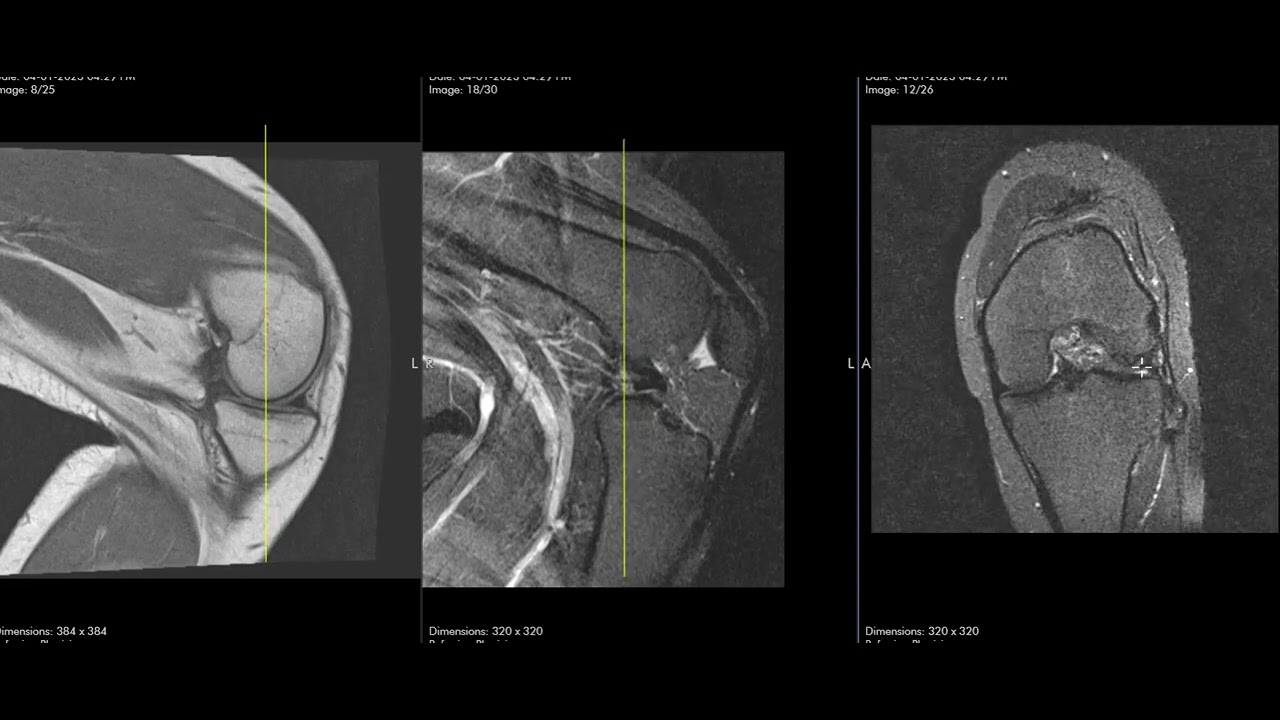

Dislocated meniscus and knee locked in flexion